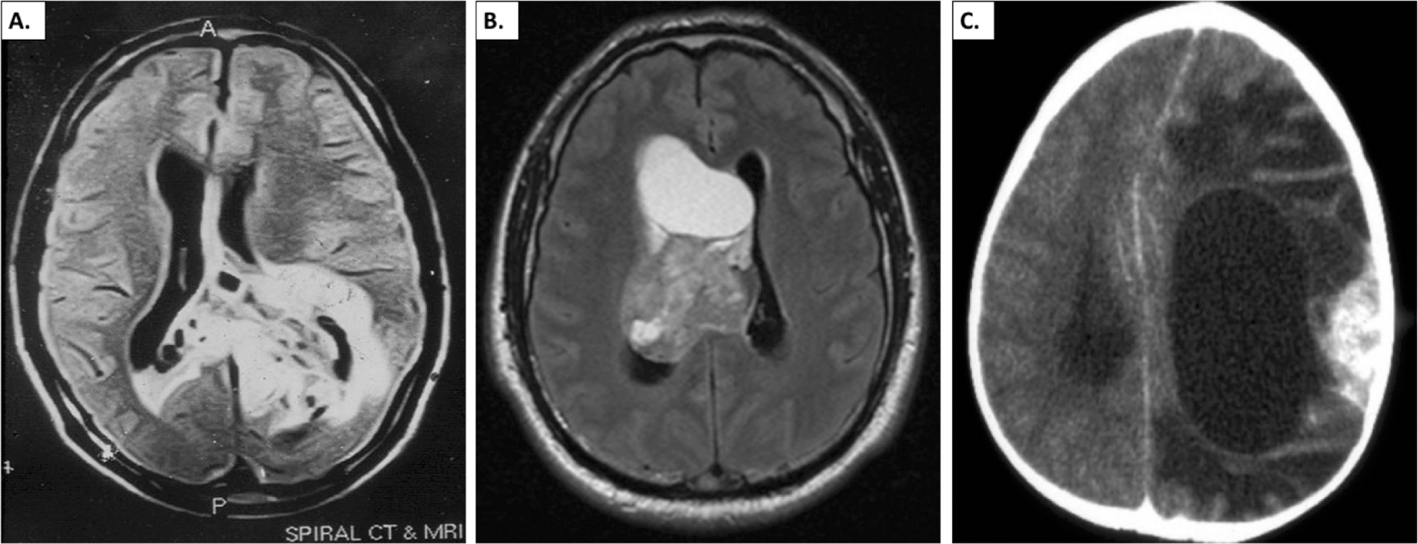

Figure 3. Radiographic appearance of glioneuronal tumors. A. Papillary glioneuronal tumor. Non-contrast magnetic resonance imaging showing hyper-intense lesion involving the left temporal and parieto-occipital regions. The tumor is crossing the midline to the right parietal region (adapted from 62). B. Axial FLAIR (fluid-attenuated inversion recovery) MR image showing a right ventricular mixed solid/cystic mass limited by the septum pellucidum and ventricular walls. With heterogeneous enhancement on post-gadolinium sequences. Provisional diagnosis of central neurocytoma, later confirmed on pathology (adapted from 63). C. Radiologic appearance of desmoplastic infantile ganglioglioma (adapted from 64).

The features of glioneuronal tumors on diagnostic imaging are highly variable. Limited data exists, hampering an in-depth analysis of radiographic-pathological correlation. Hybrid features have been noted in many tumors. In general, radiological studies acknowledge overlap of imaging features between glioneuronal tumors and other tumors, which complicates radiographic diagnosis (82). Large tumors demonstrate cystic degeneration and necrosis, hemorrhage, contrast enhancement, and regions of low apparent diffusion coefficient consistent with patterns seen with other high-grade pediatric brain tumors (83). Broadly, glioneuronal tumors are characterized by the presence of a solid/cystic mass in periventricular location with septations and a solid inner component (84) (Figure 3). Attempts have been made to radiographically classify long-term epilepsy-associated tumors, of which glioneuronal tumors form a significant component. A number of small series have described imaging features of PGNT (42, 85), RGNT (40, 41, 86), DLGNT (4547, 87), GG (56), neurocytomas (16), DNT (8). PGNT, RGNT and GNTNI were added to the WHO classification in 2007 hence imaging reviews are more recent and evolving (2). Most of these tumors are located in the supratentorial region (69%), however, spinal (23%) and disseminated disease at primary diagnosis (8%) are also described (7). They exhibit variable contrast enhancement with GNTNIs appearing mostly as solid tumors in 73% of cases; about 19% appear as cystic with a mural nodule under T2-hyperintensity and T1-hypointensity (7) (Figure 3A (62)). The most common site of glioneuronal tumors is the temporal lobe followed by frontal lobe (8). Tumors with a high Ki-67 index (≥5) are more likely to exhibit perilesional edema and ring enhancement on magnetic resonance imaging (MRI) (10). DLGNT was added to the WHO classification in 2016 and publications have increased since (1, 2, 4550, 55). In DLGNT, MRI is generally consistent with diffuse leptomeningeal enhancement predominantly and multiple cystic-solid lesions along the neural axis (49, 59, 87) but may present more atypically as well (45, 88). GGs appear cystic-solid or solid with long T1 and T2 signals with associated calcification (89). Often there is limited edema, and they may display no or mild contrast enhancement. Neurocytomas can be ventricular or extraventricular. Extraventricular neurocytomas are usually cortically based and infiltrative without peritumoral edema or intratumoral hemorrhage (Figure 3B (63)). DIA/DIG on computed tomography and MRI appear as large superficial large cerebral masses with solid and cystic areas (60). The solid component of the tumor frequently shows contrast enhancement (60) (Figure 3C (64)). Ultimately, the differential diagnosis of these findings includes low-grade glioneuronal tumors and low-grade gliomas.